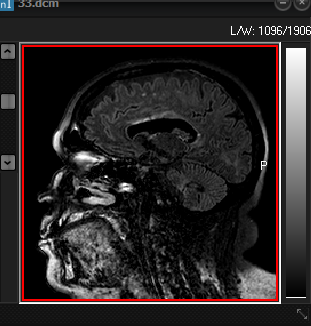

Screenshot

of original 3D volume (left) and resulting brain extracted volume (right)

after preforming a brain extraction session. The resulting extracted brain volume

overlaid on the original is shown below.